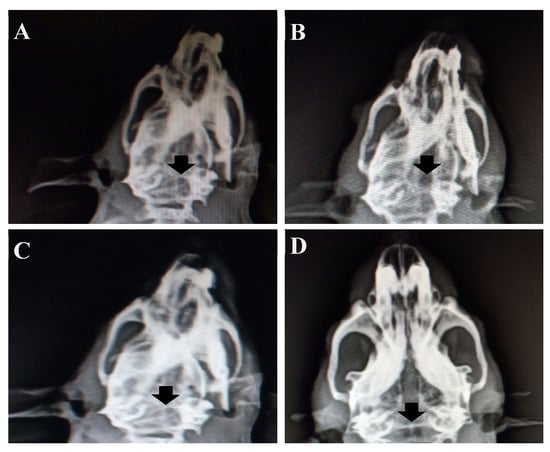

3.12.1. X-Ray Radiology Results

- ✓ In vivo animal study confirmed the effective bone formation at the 8th week of implantation of HAP-HPC-PLA grafted in the defective area with more cell differentiation when compared with the 4th week of implantation.